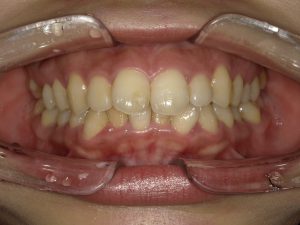

初診時の写真です。

上の前歯が大きく少し前に出ているように見られる事、また下の前歯の歯並びが気になるとの事です。